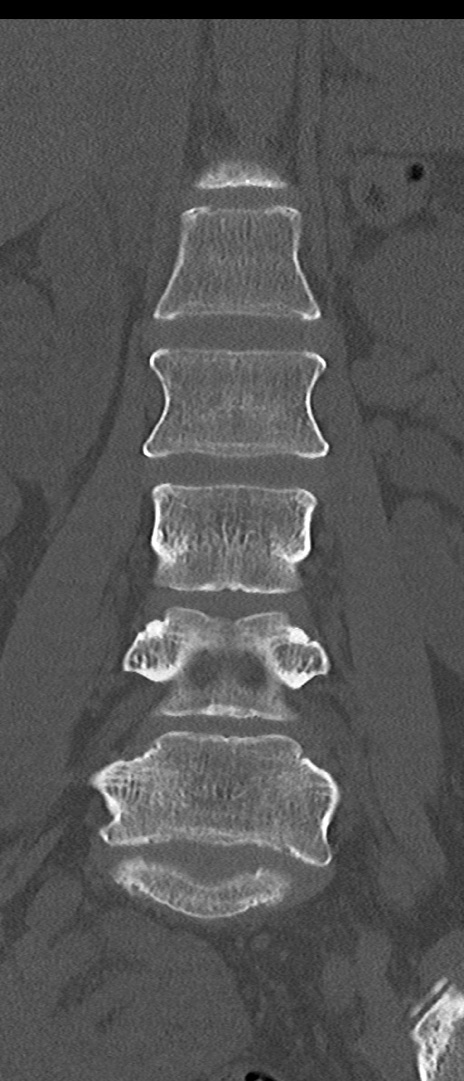

【整形】TIPS症例4 腰椎CT(冠状断像)

腰椎CT